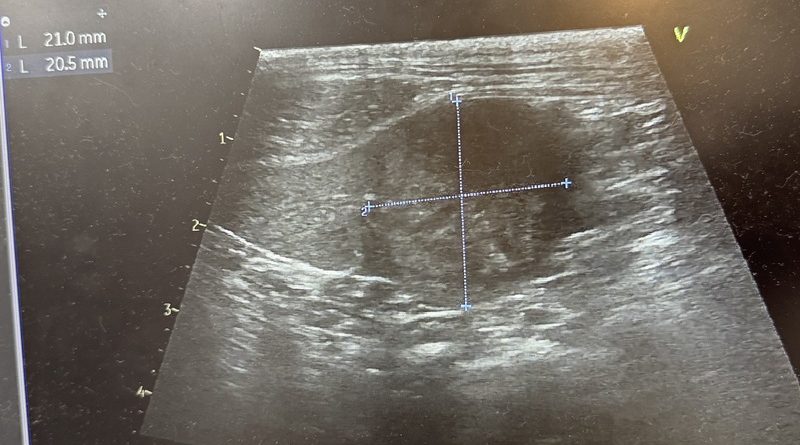

「下痢や嘔吐を繰り返したため9月30日に精密検査を行ったところ、脾臓や腹腔内に腫瘍が見つかりました。

皆さまからのご寄付は、この検査費および治療費として活用させていただきました。現在はかかりつけ医と相談しながら、手術に向けて体調を整えている段階です」